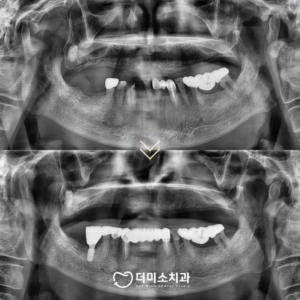

모든 치료가 마무리된

구강 내 사진과

파노라마 사진인데요.

위턱의 보험 틀니의 경우

이전 틀니에 비해 유지력이 좋아지고

형태와 교합 상태가 개선되었으며,

아래턱 앞니 역시

이전에는 앞니가 정출 되어

위턱 틀니에 불리한 힘점 작용했으나

형태가 개선되고 올바른 교합으로

마무리되었습니다.

환자분께서도 전보다 훨씬 더 편안해지고

심미적으로 변한 모습에

만족해하셨습니다.